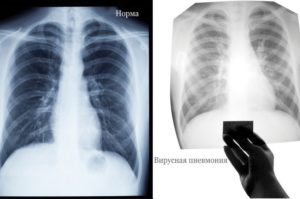

После проведения рентгенографии снимки должен изучить специалист, и на основе полученных данных и результатов других исследований сделать соответствующие выводы и поставить диагноз. В норме легкие и бронхи человека выглядят следующим образом:

- легочные доли имеют одинаковый, равномерный черный оттенок;

- в районе сердца наблюдается белый просвет;

- ребра и ключицы серые, с привычными очертаниями;

- купола диафрагмы белого цвета;

- позвоночный столб расположен в центре.

Первый признак пневмонии на рентгеновском снимке – появление очагов затемнения с неровными контурами в разных частях легкого, которые могут иметь разный размер, от 3-4-х до 12 мм.

| Рентген | Усиление лёгочного рисунка | Очаговые затемнения |

классический вариант бронхита на рентген-снимкепневмония на рентген-снимке: видно почти полное затемнение нижней доли

Несмотря на некоторые различия пневмонии и бронхита, нередко клиника бывает размытой.

В такой ситуации для установления верного диагноза необходимо сделать флюорографию или рентгенографию – это наиболее достоверный способ диагностики. По результатам рентгенограммы лечащий врач сможет легко распознать болезнь.

Худшие опасения подтвердятся, если на снимке будут отчётливые затемнения.